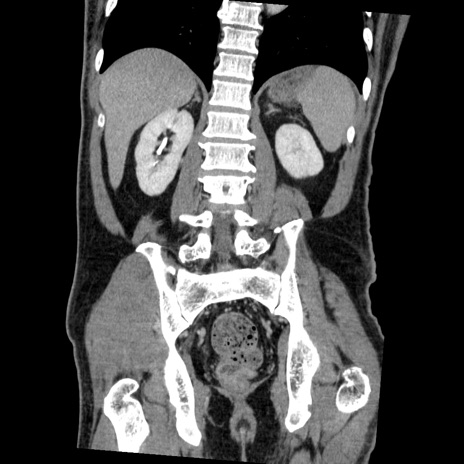

症例22(冠状断像)

【症例】50歳代男性

【主訴】腹痛

【現病歴】AVMからの被殻出血のため回復期リハ病棟入院中。 本日午後3時頃急に下腹部痛が出現した。

【既往歴】AVM、被殻出血、虫垂炎、高血圧

【身体所見】意識晴明、左半身不全麻痺、会話の理解は良好、36.5°C、腹部:膨隆、全体に板状硬、下腹部正中に圧痛点あり、反跳痛-、筋性防御不明、右下腹部にope scar

【データ】WBC 9400、CRP 0.06